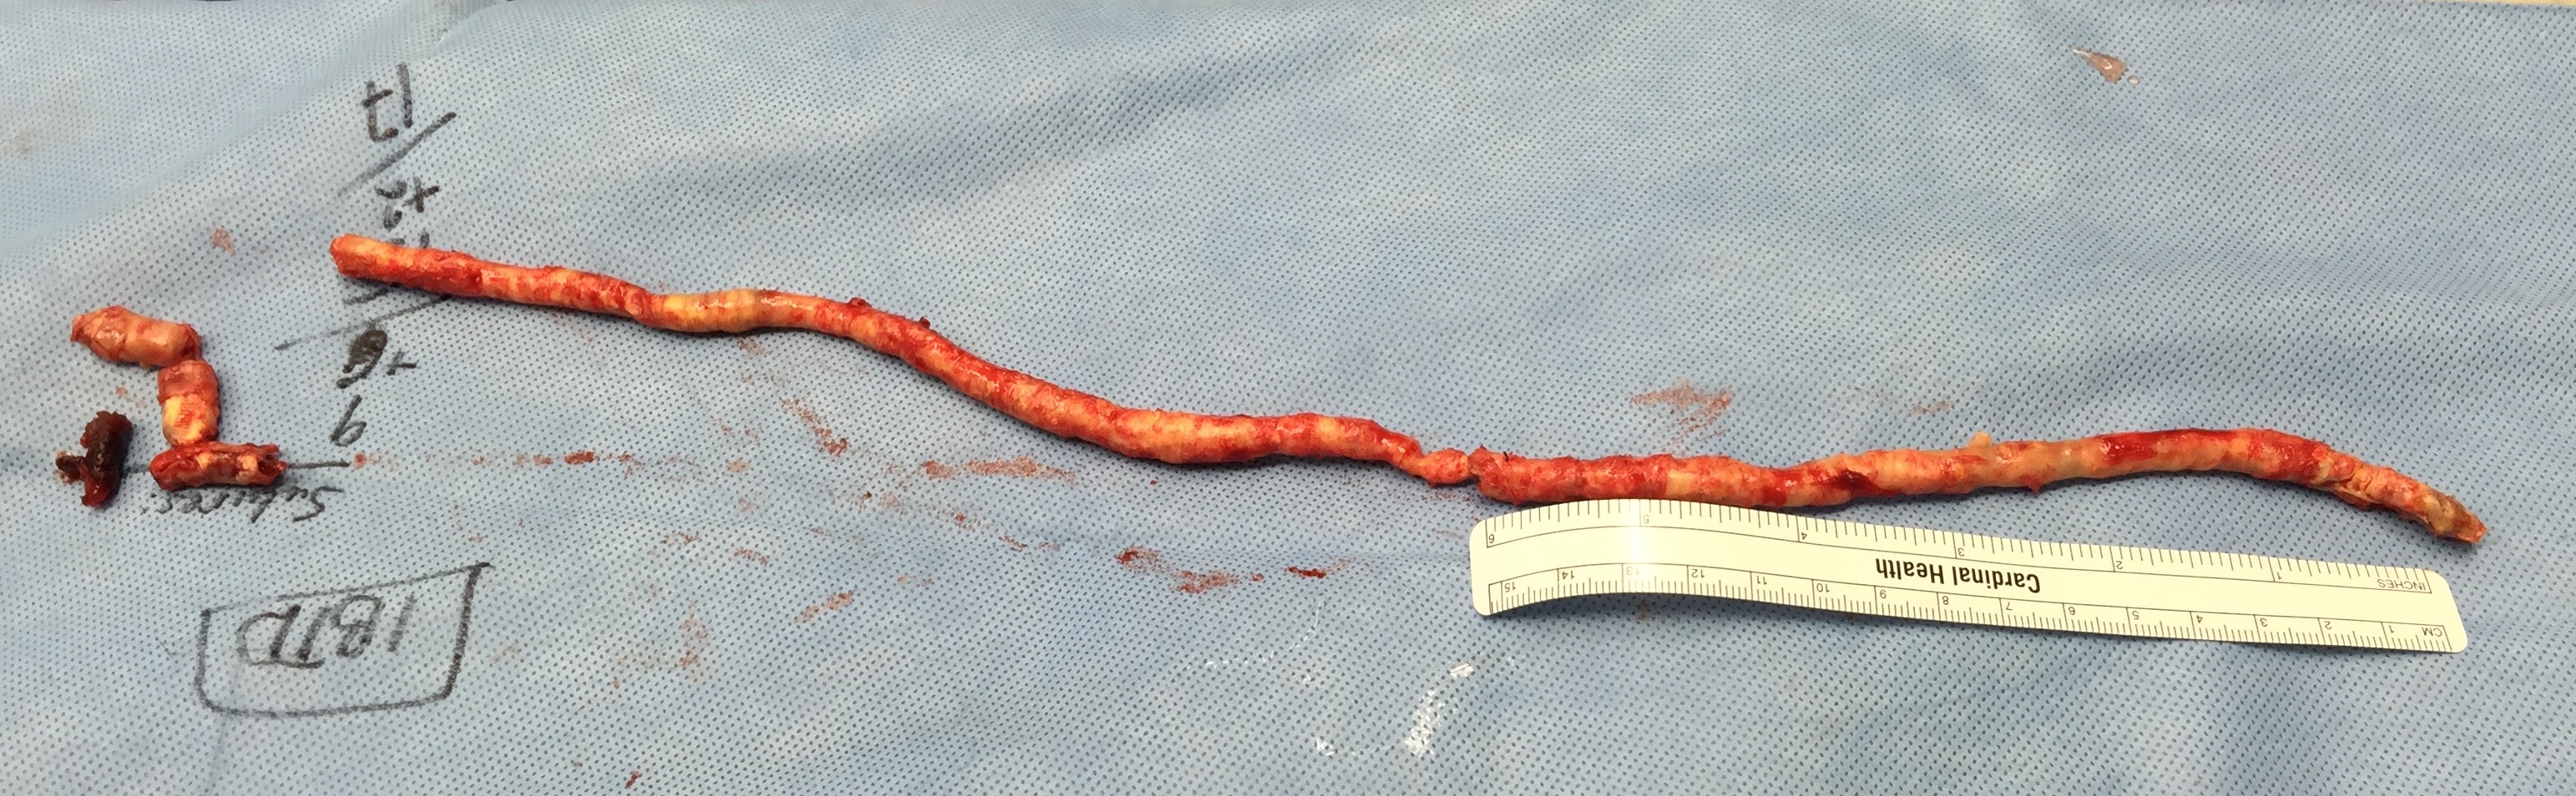

The specimen shows that the adventitia remains separated from the stents by the plaque. I rarely use tacking sutures as I feel a properly performed endarterectomy results in no plaque or well adherent mild plaque.

The patient is heparinized clamps applied, and I make the arteriotomy with a 15 blade cutting down to the stent. The aorta is cut to a point about a centimeter below the clamp. The external iliac is cut to where there is patency of the artery and the plaque is mild. The endarterectomy is performed in the same way one does a carotid or femoral, with care to find the correct endarterectomy plane outside the plaque and good end points where the plaque adheres well. The internal iliac plaque on the right was chronically occluded but was successfully removed via eversion resulting in back bleeding. I sound the artery with a dilator to make sure a dissected plaque isn’t occluding it then reclamp.